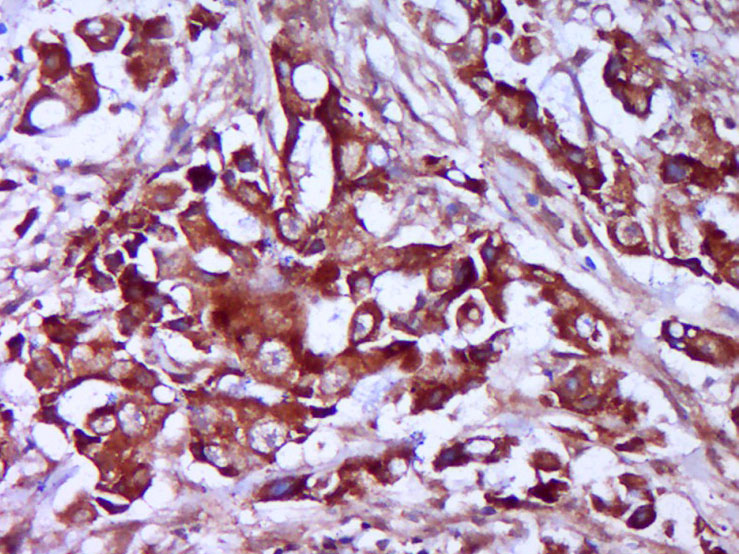

| 英文名称 | TRMT61B Rabbit pAb |

| 产品应用 | IHC-P=1:100-500, IHC-F=1:100-500, IF=1:100-500 Not yet tested in other applications. |

| 交叉反应 | Human (Cow, Horse, Sheep) |

| {IHC-P} | {1:100-500} |